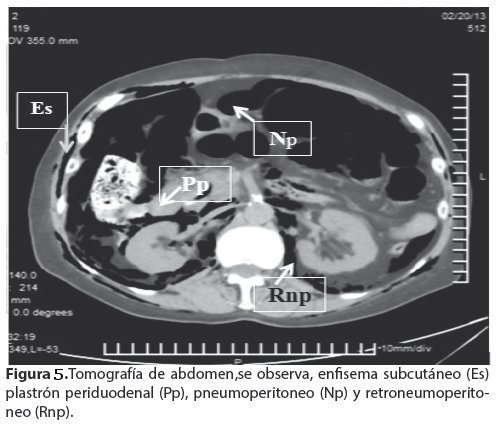

<body><![CDATA[<p align="justify"><a name="f2"></a></p>     <p align="center"><img src="/img/revistas/gmb/v37n1/a10_figura_02.jpg" width="501" height="431"></p>     <p align="justify"><font face="Verdana" size="2">La tomografía computarizada (TC); Scout (<a href="#f3">Fig. 3</a>) confirma los hallazgos anteriores, enfisema de la pared del toraco-abdominal, neumomediastino, neumotórax izquierdo, neumoperitoneo. </font></p>     <p align="justify"><a name="f3"></a></p>     <p align="center"><img src="/img/revistas/gmb/v37n1/a10_figura_03.jpg" width="503" height="448"></p>     <p align="justify"><font face="Verdana" size="2">En la TC simple de tórax en ventana mediastinica (<a href="#f4">Fig. 4</a>) se observa enfisema subcutáneo importante de la pared del tórax, neumotórax izquierdo, neumomediastino. </font></p>     <p align="justify"><a name="f5"></a></p>     <p align="center"><img src="/img/revistas/gmb/v37n1/a10_figura_04.jpg" width="498" height="343"></p>     <p align="justify"><font face="Verdana" size="2">TC de abdomen (<a href="#f5">Fig. 5</a>), se observa, enfisema subcutáneo (Es) plastrón periduodenal (Pp), pneumoperitoneo (Np) y retroneumoperitoneo (Rnp). Con la sospecha clí</font><font face="Verdana" size="2">nica e imagenológica de perforación de víscera hueca, se somete a la paciente a laparotomía exploradora de urgencia, con hallazgo de perforación del duodeno y plastrón periduodenal. Se realiza la reparación per prima, mediante duodenorrafia y evacuación de la colección y drenaje del mismo.</font></p>     <p align="justify"><a name="f5"></a></p>     ]]></body>